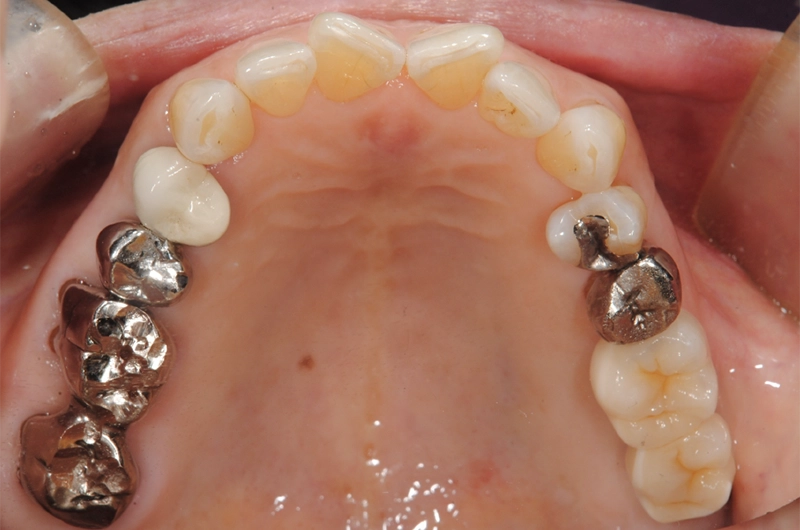

| 主訴 | 歯が抜けている。 入れ歯のところをインプラントしたい |

|---|---|

| 診断名 | 歯の欠損、義歯不適合 |

| 年齢・性別 | 63歳・男性 |

| 治療期間・回数 | 1年3ヶ月・33回 |

| 治療方法 | 精密根管治療、ジルコニアクラウン、GBR、インプラント、ホワイトニング |

| 費用 | 3,949,000円 最高プラン (費用を抑えたプランも提案可能) |

| 治療上のリスク |

|